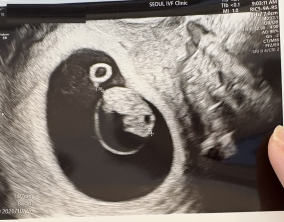

임신 수치 16, 9주차 기적의 기록

서울IVF에서는 단순히 배아 생성과 이식만 해주시는 것이 아니라, 제 생활 전반까지 신경 써주셨습니다. 휴식기에도 그저 기다리는 것이 아니라 항노화에 도움이 되는 링겔을 처방…